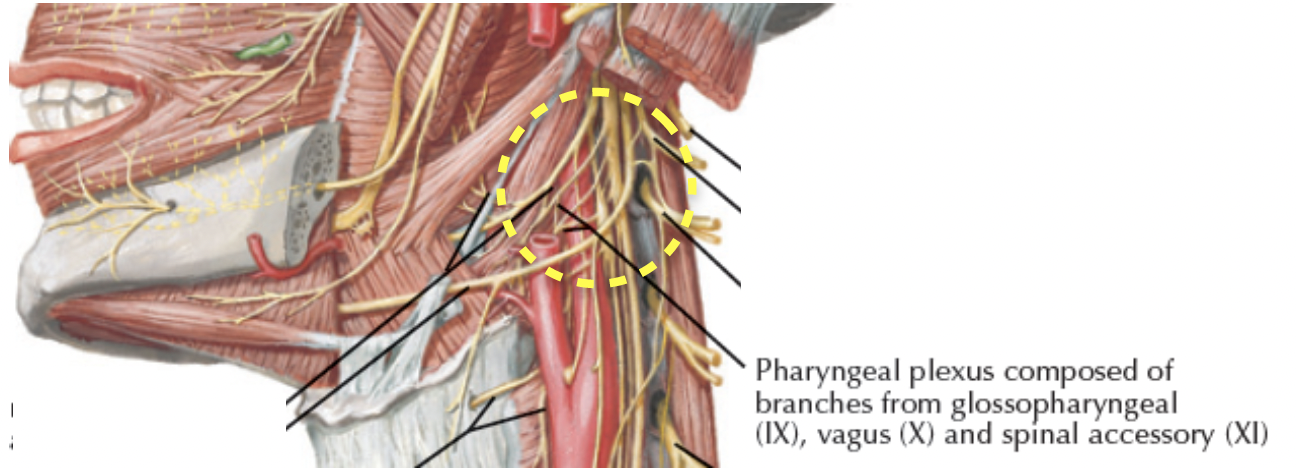

Pharyngeal plexus

- CN IX

- 主要 Sensor

- Stylopharyngeus m.

- CN X

- 主要 Motor

- Sup. laryngeal n.

- CN XI

- Motor

Others

- Recurrent laryngeal branch of the vagus

- Part of Inf. constrictor m.

- Pharyngeal n.

- Sensor of nasopharynx & the auditory tube

- CV V3

- Tensor veli palatini